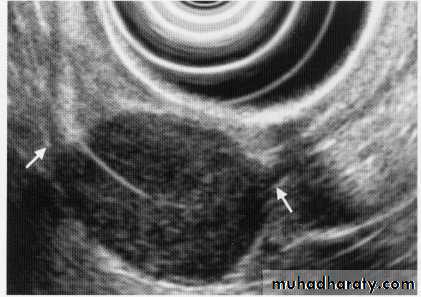

Leiomyoma EUS